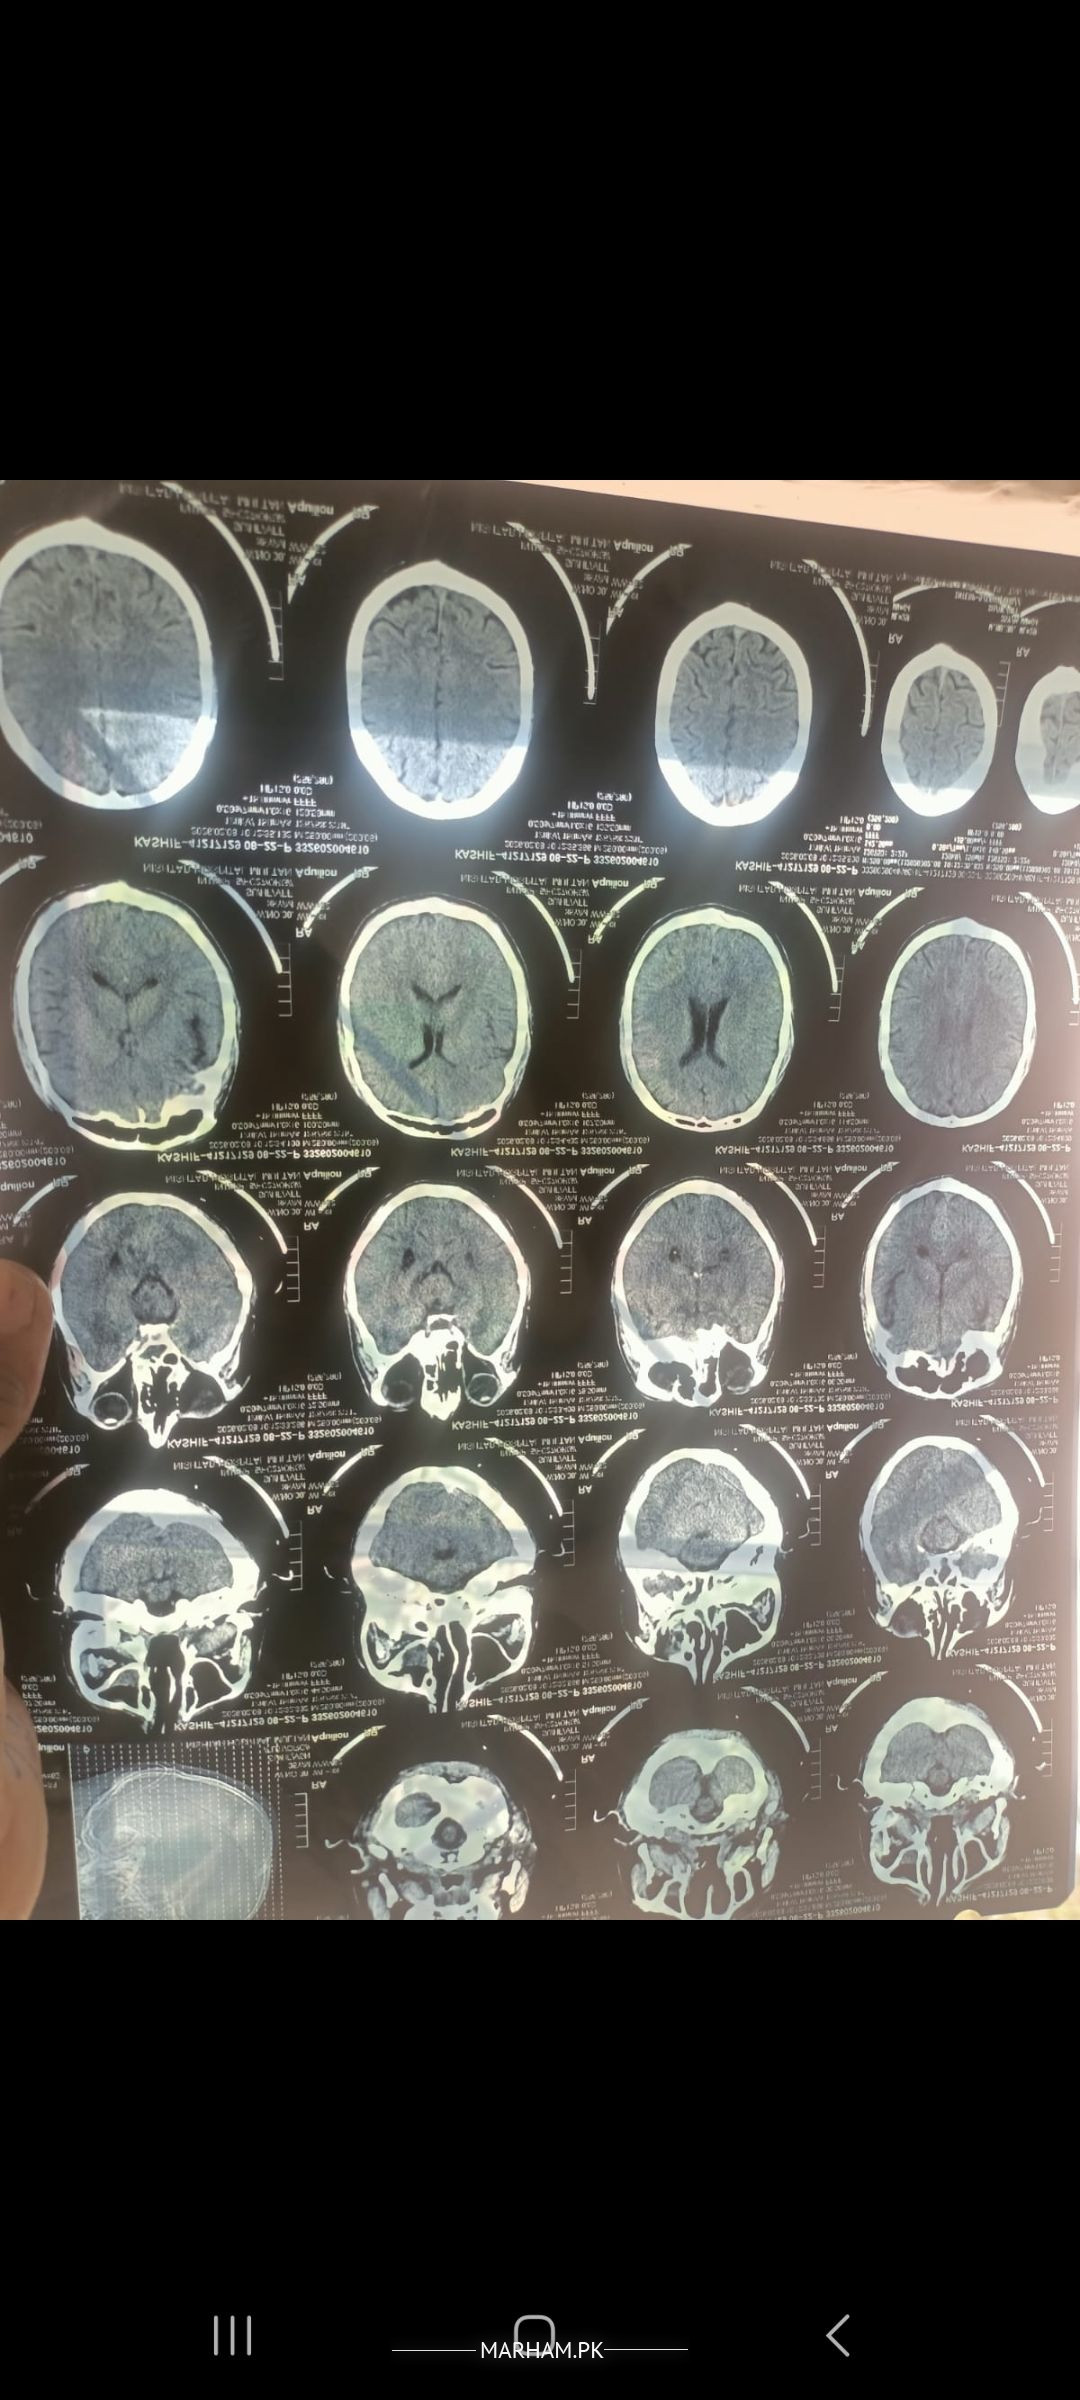

Asking For Husband, Male 38, ameer ul deen park lahore canty

plese see these reports and temm me the actual issue in detail please.

CT scan appears to be OK but there are some hypodense areas that need clarification. Also correlation with detailed history and examination is necessary. An MRI will be needed for better visualization

CT looks okay. Your headaches are likely a clinical diagnosis and not a radiological one. Kindly consult a Neurologist (online is sufficient) for further management.